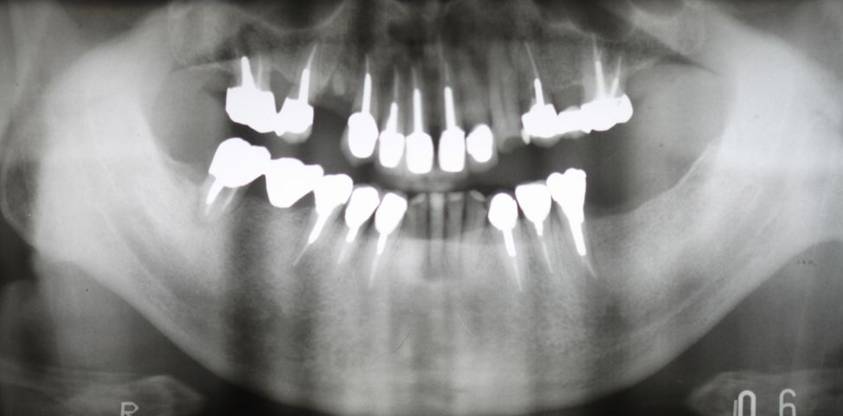

歯周病で抜歯せざるを得ず、インプラントを希望されたケース(使用インプラントはスプライン)

術前。すべての歯が歯周病の末期状態でブリッジ全体がうごいて噛めないとの訴え。右上の犬歯が腫れていました

固定式のブリッジが入っていましたが歯周病で動いています

下顎前歯部には歯石の沈着がみられます

術前パノラマレントゲン写真。根の周りが黒くなり、骨がなくなっていることがわかります